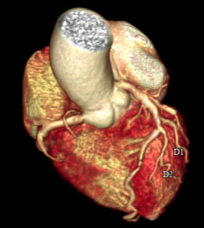

Công nghệ tim mạch Aheart

Phương pháp chỉnh sửa ECG

Khám phá nhiều hơn, đi sâu vào từng chi tiết

Hình ảnh lâm sàng